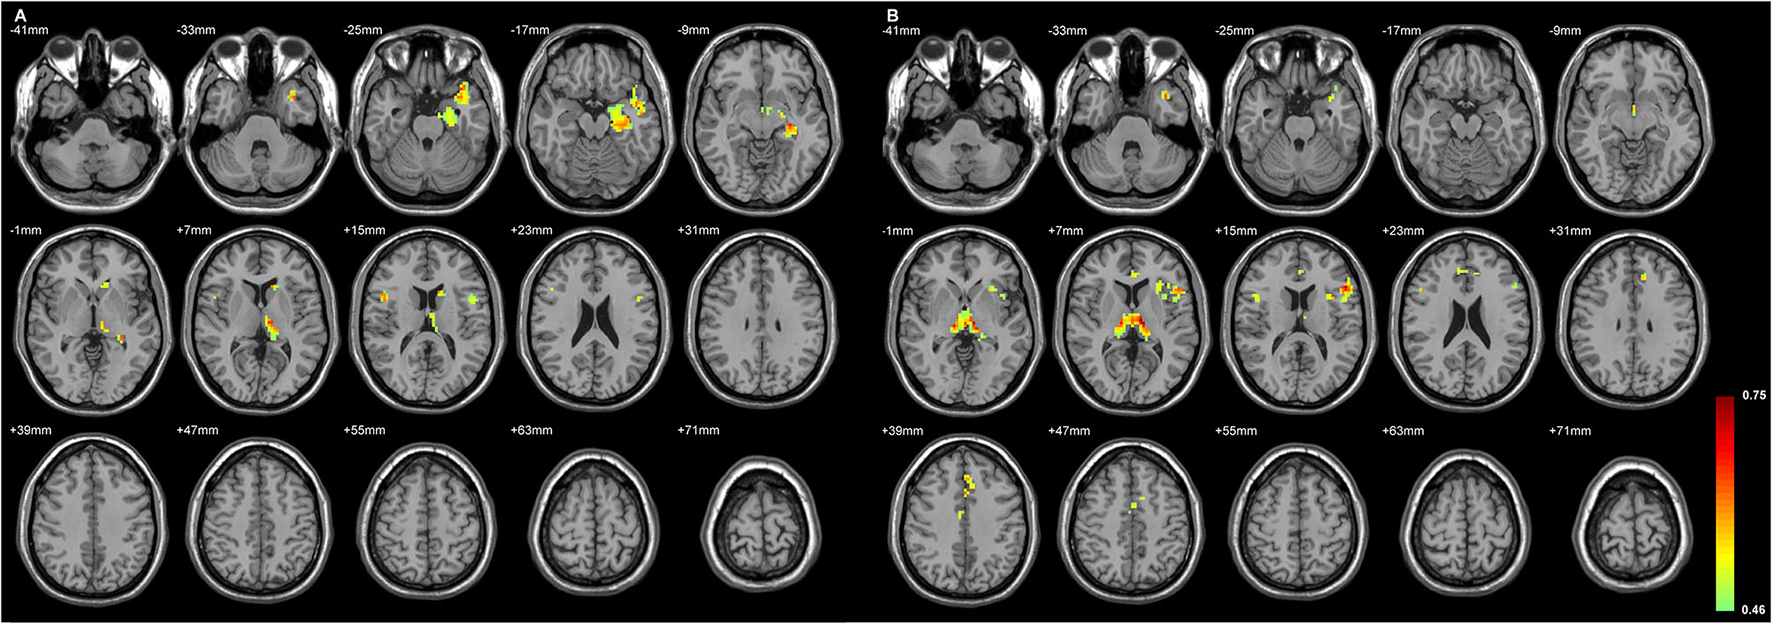

The Status of the Volume Loss of Both Sides of Thalamic Subfield Was Primarily Related to the Ipsilateral Inferior Frontal GMD Changes

Figures 4, 5 exhibited that the distribution of the neocortical atrophy was strongly associated with the amount of the sum of volume loss of the thalamic subfields on each side. GMD of the ipsilateral inferior frontal gyrus was positively related to each side of thalamic subfield volume changes in L-TLE. Meanwhile, it was negatively correlated with the volume loss of each side of thalamic subfields in R-TLE. In addition to the thalamus, GMD of the left caudate nucleus was another deep structure that was related to the thalamic subfield volume changes in L-TLE (Table 6).

Figure 5

The regions with their GMD related to the (A) left LD-CL and the (B) right AV-LD-LP-VA-Vamc-CeM-MV(Re)-MDl-L-Sg volume changes in R-TLE. Both positive and negative relationships are depicted, and are mostly located in the right frontal lobe. GMD of the right inferior frontal gyrus was negatively related to each side of thalamic subfield volume changes in R-TLE. Differences with a p < 0.01 were considered significant (with a threshold p < 0.01 and a minimum cluster size = 354 voxels, as determined by the AlphaSim correction).

The GMD changes in the ipsilateral side of the epileptogenic zone were more related to the volume changes of the thalamic subfields than the contralateral side in L-TLE. In contrast, R-TLE affected GMD more equally on both sides, but the effect was less extensive compared with the L-TLE. Most cortical volumes showed a positive relationship with the thalamic volumes, and only a few had a negative association in R-TLE (Table 7).